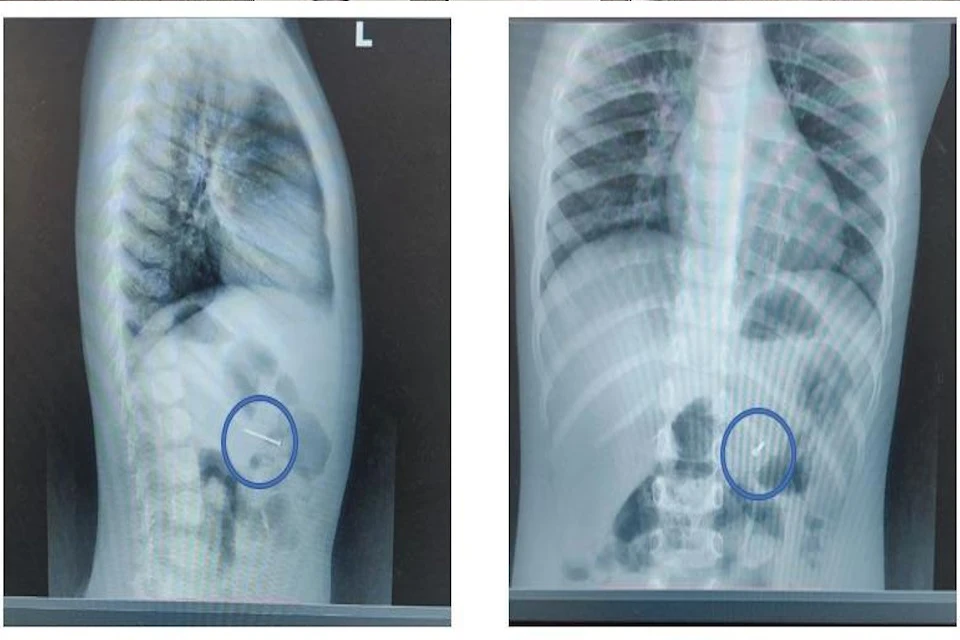

Фото: Министерство здравоохранения Московской области.

Медики оперативно провели диагностику: рентгенография подтвердила наличие металлического предмета в желудке. Врач-эндоскопист Руслан Мусаев пояснил, что гвоздь мог повредить стенки пищевода или желудка, вызвав опасные осложнения.

С помощью гастроскопии врачи аккуратно извлекли инородный предмет эндоскопическими щипцами за 20 минут, избежав хирургического вмешательства.